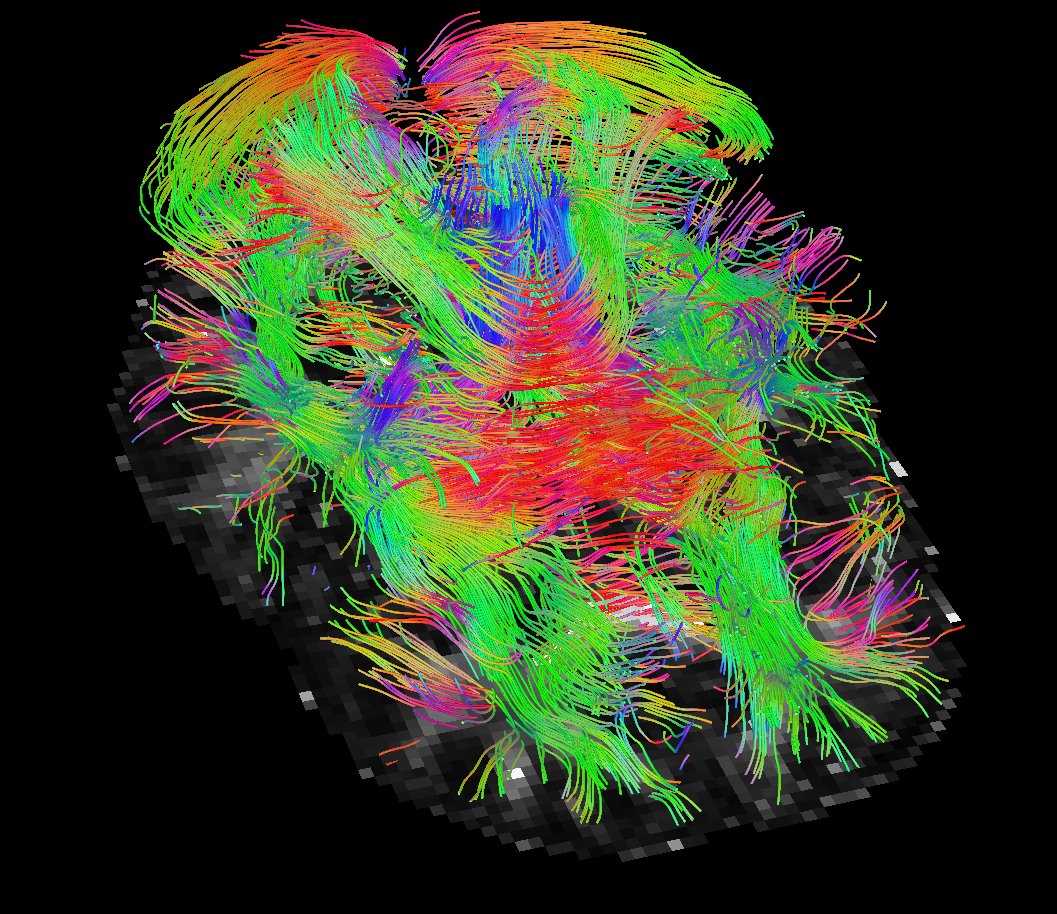

The numerical results are in Table 1 and Figures 3–5, with the first of the figures showing the colour-coded principal eigenvector of the reconstruction, the second showing the fractional anisotropy and principal eigenvectors, and the last one the errors in the latter two, in a colour-coded manner. All plots are masked to represent only the non-zero region. The field of fractional anisotropy is defined for a field of 2-tensors on as

As we can see, the non-linear approach (3.2) performs overall the best by a wide margin, in terms of the pointwise Frobenius error, i.e., error in . This is expressed as a PSNR in Table 1. What is, however, interesting, is that the constraint-based approach (3.5) has a much better reconstruction of the principal eigenvector angle, and a comparable reconstruction of its magnitude. Indeed, the 95% confidence interval in Figure 3(g) and Figure 4(g) suggests a nearly perfect reconstruction in terms of smoothness. But, the Frobenius PSNR in Table 1 for this approach is worse than the simple unregularised inversion by regression. The problem is revealed by Figure 5(f): the large white cloudy areas indicate huge fractional anisotropy errors, while at the same time, the principal eigenvector angle errors expressed in colour are much lower than for other approaches. Good reconstruction of the principal eigenvector is important for the process of tractography, i.e., the reconstruction of neural pathways in a brain. One explanation for our good results is that the regulariser completely governs the solution in areas where the error bounds are inactive due to generally low errors. This results in very smooth reconstructions, which is in the present case desirable as our synthetic tensor field is also smooth within the helix.